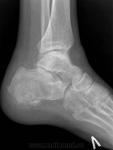

Здравствуйте! Я - молодой доктор, оставшийся один в отделении на целый месяц. Непонятных мне снимков много, вот отдин из них. Женщина 1938г.р., направлена на снимки голеностопного сустава с диагнозом: Артроз. Артроза не вижу, но пяточная кость вызывает подозрения. Что это может быть? Помогите разобраться.

Киста пяточной кости.

+1. Для опыта по-рекомендовал бы сделать аксиальный снимок и томограммы.

На самом деле, я бы в заключение вынесла "кисту" и рекомендовала МРТ